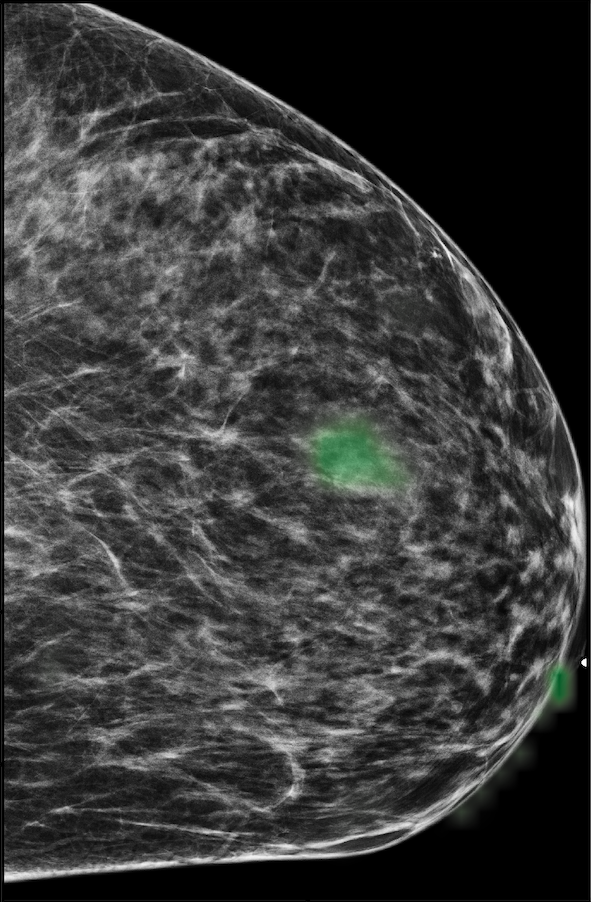

To evaluate the localization performance of GMIC, we select the model with the highest DSC for malignancy localization using the validation set. During inference, we upsample saliency maps using nearest neighbour interpolation to match the resolution of the input image. Our best localization model achieves a mean test DSC of 0.325 (std:0.231) for localization of malignant lesions and 0.240 (std:0.175) for localization of benign lesions. The best localization model achieves an AUC of 0.886/0.78 on classifying malignant/benign lesions. We observe that localization and classification performance are not perfectly correlated. The trade-off between classification and localization has been discussed in the weakly supervised object detection literature [15, 62, 82].

In Figure 7, we visualize saliency maps for four samples selected from the test set. In the first two examples, the saliency maps are highly activated on the annotated lesions, suggesting that our model is able to detect suspicious lesions without pixel-level supervision. Moreover, the attention is highly concentrated on ROI patches that overlap with the annotated lesions. In the third example, the saliency map for benign findings identifies three abnormalities. Although only the top abnormality was escalated for biopsy and hence annotated by radiologists, the radiologist’s report confirms that the two non-biopsied findings have a high probability of benignity and a low probability of malignancy. In the fourth example, we illustrate a case when there is some level of disagreement between our model and the annotation in the dataset. The malignancy saliency map only highlights part of a large malignant lesion with segmental coarse heterogeneous calcifications. This behavior is related to the design of : a fixed pooling threshold cannot be optimal for all sizes of ROI. The impact of is further studied in 3.6. This example also illustrates that while human experts are asked to annotate the entire lesion, CNNs tend to emphasize only the most informative regions. While no benign lesion is present, the benign saliency map still highlights regions similar to that in the malignancy saliency map, but with a lower probability than the malignancy saliency map. In fact, calcifications with this morphology and distribution can also result from benign pathophysiology [42].